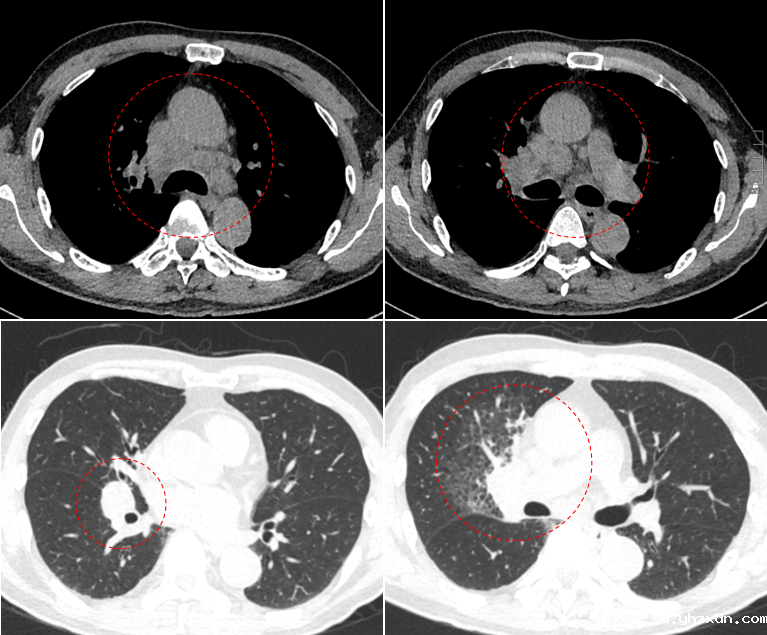

(图二)

胸部CT结果显示,L先生右肺门区域存在明显肿块,导致右肺中叶出现阻塞性肺炎和阻塞性肺气肿。此外,纵膈部位多发淋巴结肿大,部分淋巴结甚至出现融合(图二)。通过三维重建技术,医生发现肿块已跨越斜裂生长,侵及右肺中叶及下叶(图三)。